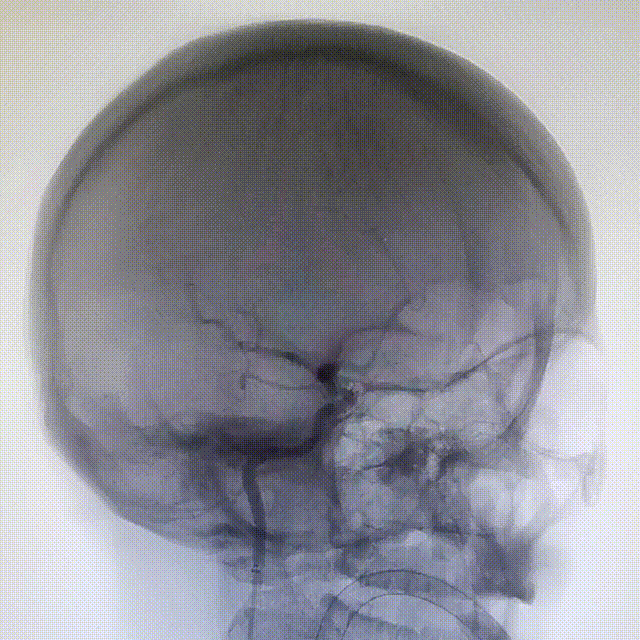

术后3D造影:支架打开充分,全程贴壁,各分支血管血流通畅,可看到内翻的Mark点也被Evolve贴到了血管壁上,充分体现了Evolve足够强的径向力,预示着Evolve对动脉瘤合并狭窄应用或许是一个不错的选择。